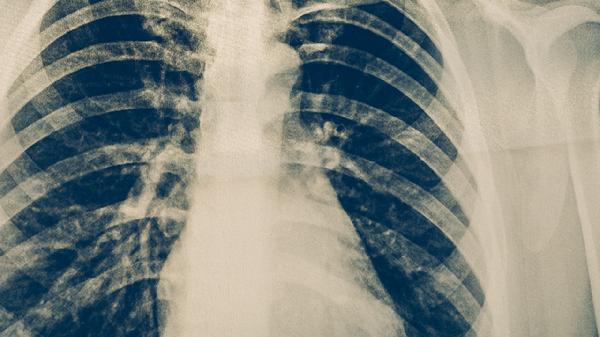

康复期间建议多吃高蛋白的食物,如鱼肉、豆制品,同时搭配富含维生素C的水果,比如猕猴桃和橙子。每天进行30分钟左右的散步等低强度活动,注意观察体温和咳嗽的变化。如果持续低烧或咳出黄脓痰超过三周,应及时复查胸部X光,排除其他感染的可能性。在恢复初期尽量避免去人多的地方,规范用药也有助于降低复发的风险。